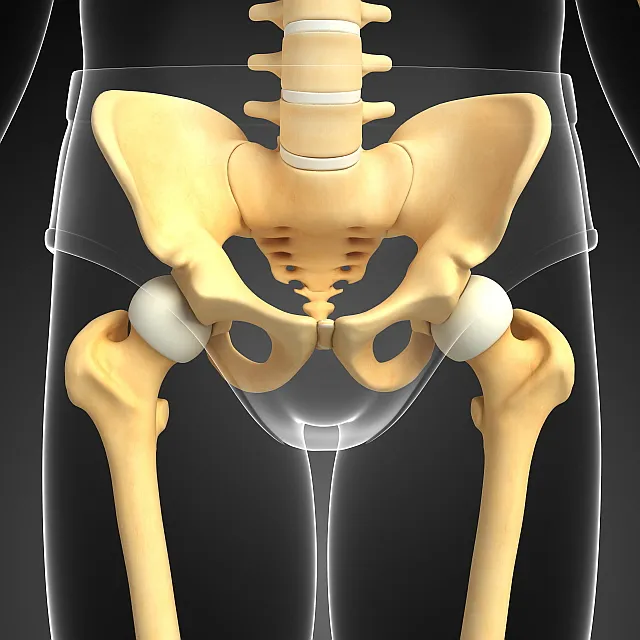

고관절은 엉덩이 관으로도 알려져 있으며, 인체에서 가장 큰 관절입니다. 그러므로 고관절에 문제가 생기면 종종 무릎 관절 문제보다 더 심각한 결과와 증상을 초래하는 경우가 많습니다. 무릎에 통증이 있는 경우 목발이나 다른 보조 기구를 통해 이동이 가능하지만, 고관절 장애는 종종 사람을 완전히 움직이지 못하게 할 수 있습니다.

고관절은 골반과 대퇴골을 연결하여 척추와 체중을 지탱하고 하체를 지지하는 역할을 수행하며, 지속적인 압력을 받는 취약한 부위입니다. 걸을 때는 체중의 약 4배, 달리기를 할 때는 약 5배, 계단을 오를 때는 최대 8배의 하중이 고관절에 가해져 통증이나 질환이 발생하기 쉬운 부위입니다.